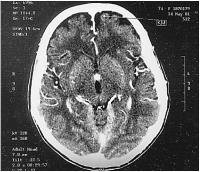

Hypernephrom-Metastase

Abbildung 3: Metastase eines Hypernephroms

Keywords:

Hypernephrom

,

Magnetresonanztomographie

Metastase

Neurochirurgie